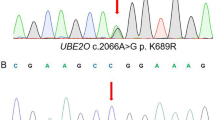

Targeted next-generation sequencing revealed that all three patients were negative for mutations in the five currently clinically associated HH genes. Further analysis identified a tri-nucleotide duplication in BMP6, c.353-355dupAGC (NM_001718.4), resulting in the in-frame duplication of glutamine p.Q118dup (NP_001709.1), which was confirmed by Sanger sequencing. The nomenclature for this variant is noted in three different forms across various datasets: dbSNP rs771616962 refers to this variant as p.Q118_L119insQ, wANNOVAR, and the NHLBI Exome Sequencing Project (http://evs.gs.washington.edu/EVS/) (ESP) dataset as p.E112delinsEQ and Exome Aggregation Consortium database (ExAC) [12] as p.Gln115dup. While all of these references result in the same outcome, extension of the poly-Q stretch, the various designations may cause underestimation of its population frequency. This variant, or its pseudonyms, is not present in the 1000 Genomes database; however, it is present in the ESP (MAF = 0.016) and ExAC (MAF = 0.041).